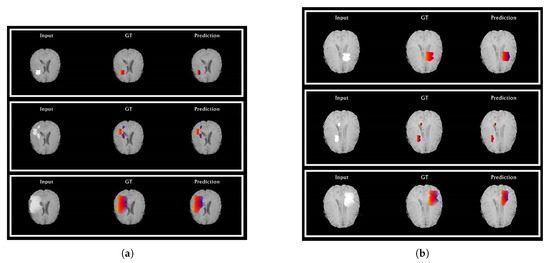

5. Experimental Results and Discussion